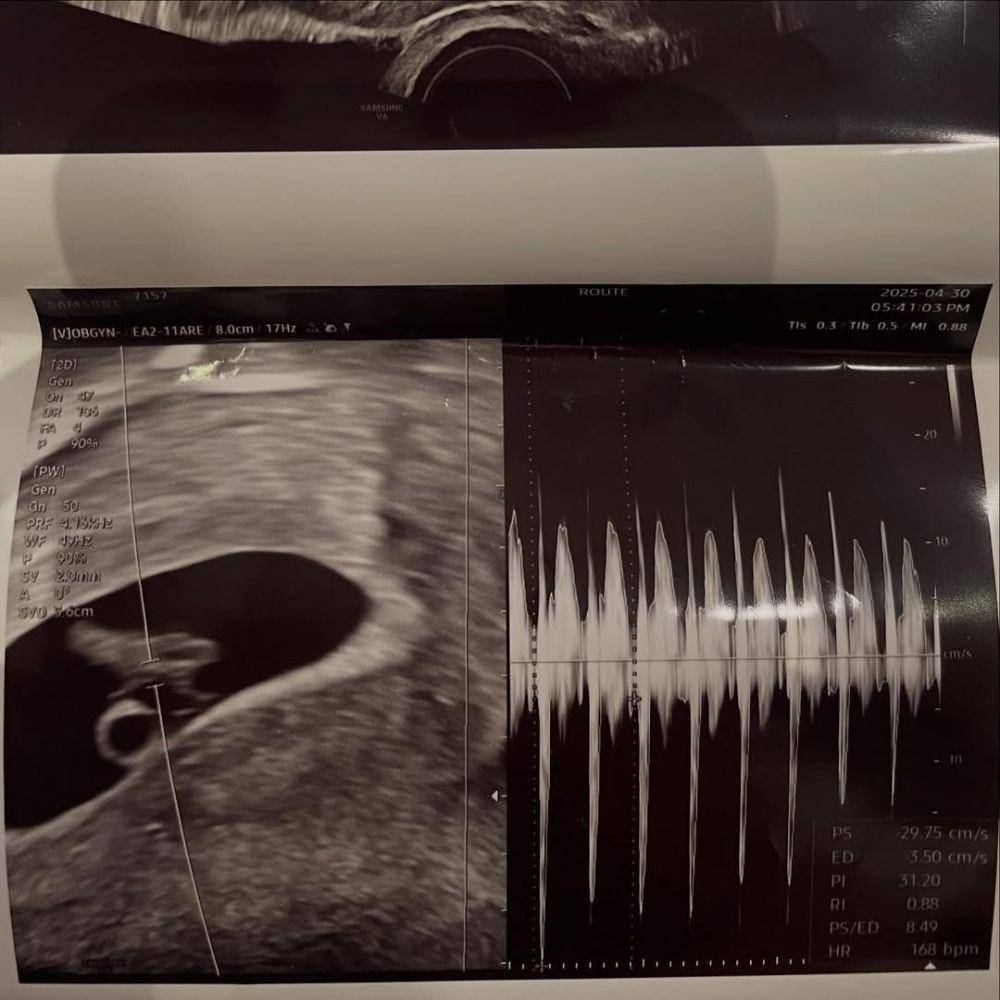

Seo Min Jae, mantan peserta Heart Signal, mengaku sedang mengandung anak pertamanya. Ia mengumumkan kabar ini lewat unggahan foto USG beserta sejumlah momen mesranya dengan sang kekasih, Jung Rae Sung.